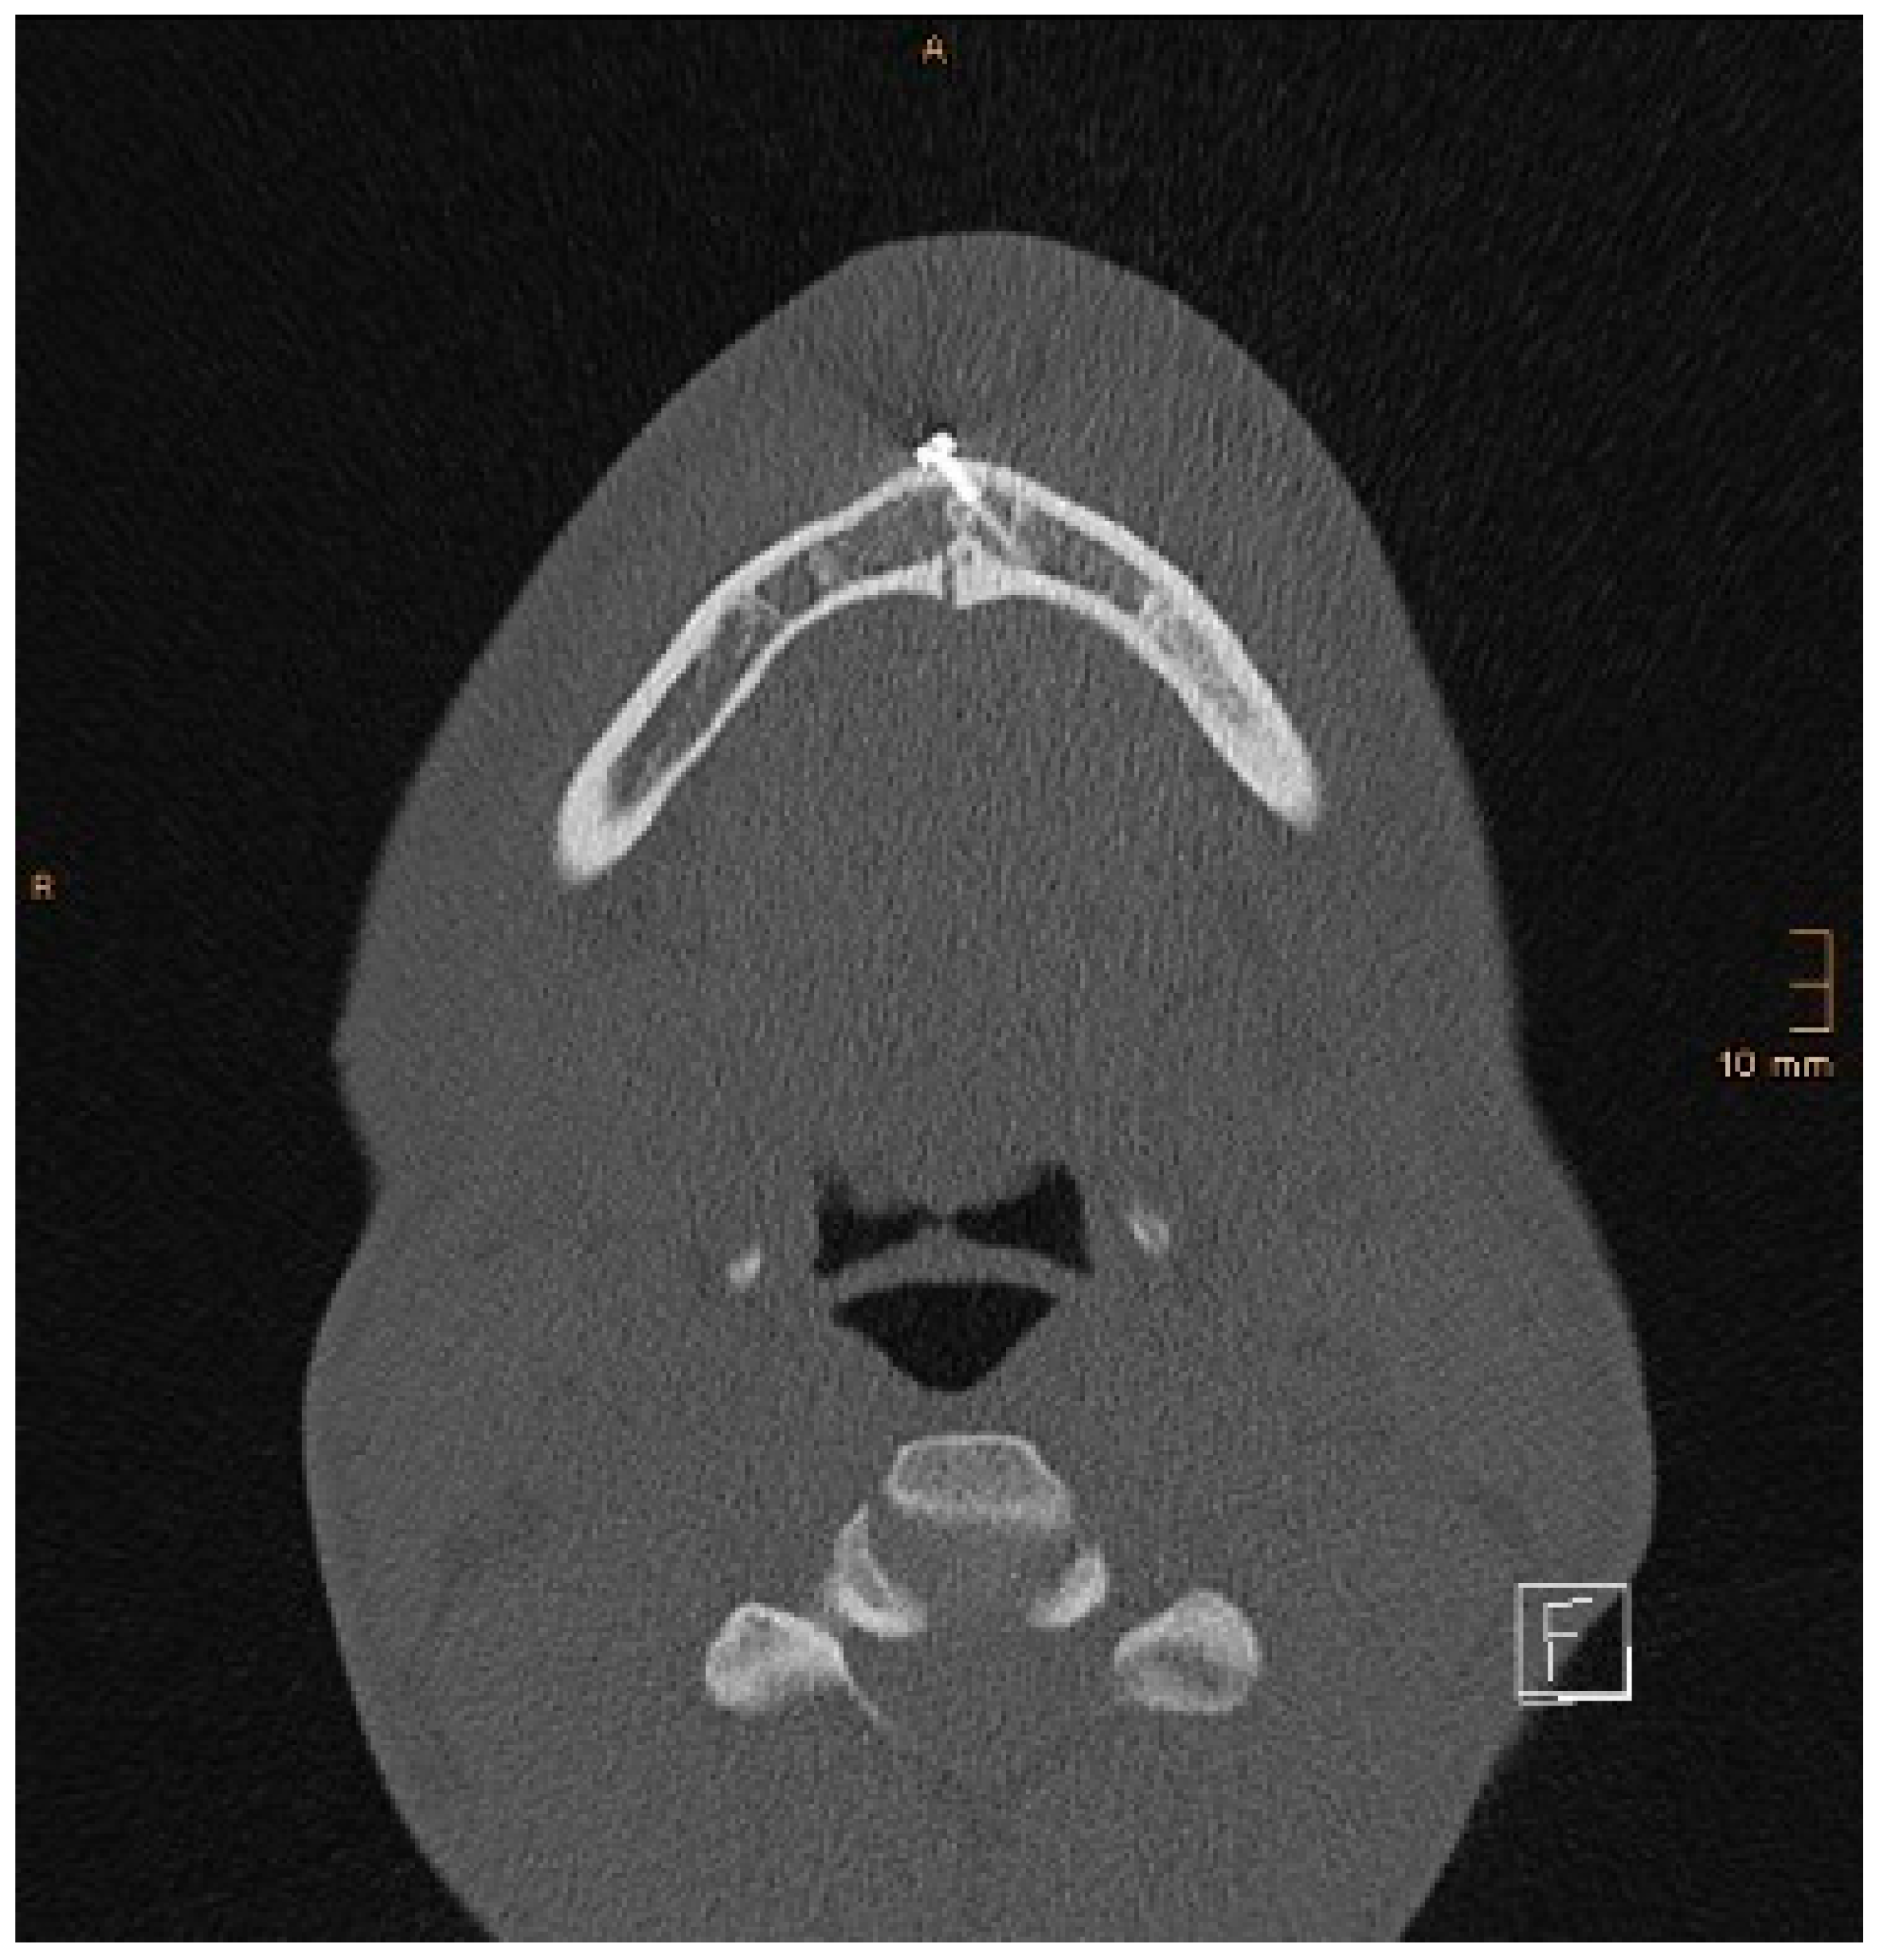

Figure 9. Axial CT scan showing the same patient as in Figure 8. A lingual gap is present after ORIF of the mandibular body fracture, contributing to the inability to reduce the condylar fracture correctly.